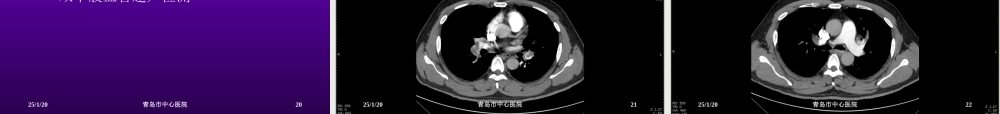

急性胸痛的患者急性胸痛的患者44例例李长江青岛市中心医院2014.12.21病例病例11患者XXX,男,45岁。突发胸痛、大汗、晕厥,家属呼叫“120”出诊,10分钟到达现场现场查体:意识不清,血压测不到,未触及大动脉搏动,无自主呼吸心电图:室颤25/1/202青岛市中心医院接下来怎么处理?接下来怎么处理?25/1/203青岛市中心医院心肺复苏心肺复苏立即360J非同步电除颤胸外心脏按压,气管插管抢救10分钟后心跳恢复,气囊辅助呼吸,返院25/1/204青岛市中心医院来院后情况来院后情况意识不清,烦躁不安,自主呼吸微弱,给予呼吸机辅助呼吸(SIMV模式)血压:140/120mmHg,双侧瞳孔不等大,皮肤湿冷,双肺呼吸音粗,未闻及干湿性啰音。HR:110次/分,律齐追问家属患者病史:高血压10余年,未治疗。酗酒,吸烟史20余年,每日20支25/1/205青岛市中心医院辅助检查辅助检查血常规、电解质、血糖、肾功无异常指端血氧饱和度92%心电图:aVR导联ST段抬高0.2mV,Ⅱ、Ⅲ、aVF、V1-6导联ST段压低0.2-0.3mV颅脑CT排除脑出血、脑血栓25/1/206青岛市中心医院诊断?诊断?急性冠脉综合征?肺栓塞?主动脉夹层?25/1/207青岛市中心医院急性冠脉综合征(急性冠脉综合征(ACSACS)?)?病人发病时有胸痛、大汗,继而晕厥,室颤心电图:aVR导联ST段抬高0.2mV,Ⅱ、Ⅲ、aVF、V1-6导联ST段压低0.2-0.3mV不具备急诊PCI的指征25/1/208青岛市中心医院肺栓塞?肺栓塞?病史符合急查血气分析、D-二聚体强化CT扫描可明确25/1/209青岛市中心医院主动脉夹层?主动脉夹层?剧烈胸痛、大汗、晕厥既往有高血压病史,未系统治疗强化CT扫描可确诊25/1/2010青岛市中心医院主动脉主动脉CTACTA25/1/2011青岛市中心医院主动脉主动脉CTACTA25/1/2012青岛市中心医院主动脉主动脉CTACTA25/1/2013青岛市中心医院主动脉主动脉CTACTA25/1/2014青岛市中心医院诊断:主动脉夹层诊断:主动脉夹层病情危重,死亡率极高维持生命体征降血压降至可耐受的低值(90/60mmHg)心率降至可耐受的低值(60次/分)外科手术治疗25/1/2015青岛市中心医院病例病例22患者XXX,男,48岁,出租车司机突发胸痛、胸闷半小时来院既往有高血压病史,规律治疗25/1/2016青岛市中心医院来院后情况来院后情况神志清,口唇轻度紫绀血压:140/80mmHg,双肺呼吸音粗,未闻及干湿性啰音。HR:120次/分,律齐,未闻及病理性杂音。腹平软,肝脾肋下未及,无压痛、反跳...